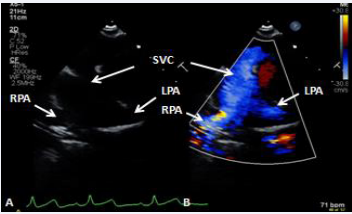

Figure 25 Selected video frames from suprasternal notch view demonstrating bidirectional Glenn shunt; the superior vena cava (SVC) is shown emptying into the right (RPA) and left (LPA) pulmonary arteries by color flow imaging (A). Low Doppler flow velocity across the shunt (B) indicates unobstructed Glenn [69].

Figure 25 :Selected video frames from suprasternal notch view demonstrating bidirectional Glenn shunt; the superior vena cava (SVC) is shown emptying into the right (RPA) and left (LPA) pulmonary arteries by color flow imaging (A). Low Doppler flow velocity across the shunt (B) indicates unobstructed Glenn [69].

Figure 26 Selected video frames from suprasternal notch view demonstrating bidirectional Glenn shunt; the superior vena cava (SVC) is shown emptying into the right (RPA) and left (LPA) pulmonary arteries by two dimensional (A) and color flow imaging (B) [69].

Figure 26: Selected video frames from suprasternal notch view demonstrating bidirectional Glenn shunt; the superior vena cava (SVC) is shown emptying into the right (RPA) and left (LPA) pulmonary arteries by two dimensional (A) and color flow imaging (B) [69].

Echocardiographic and angiographic examples of the bidirectional Glenn procedure are shown in Figures 25-28.